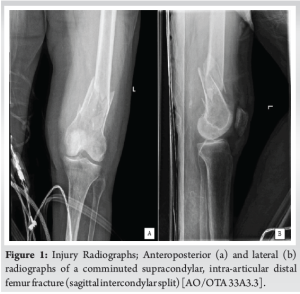

The patient was a 99-year-old female, a community ambulator with a cane, who presented after a fall from a standing height. Her past medical history was notable for hypertension, hyperlipidemia, chronic kidney disease stage 3A, and anemia. There was an obvious deformity of the left thigh as well as a punctate wound over the anterior distal thigh measuring two centimeters. She had a normal distal neurovascular examination. Plain radiographic images were obtained of her left femur and knee demonstrating a comminuted supracondylar distal femur fracture with a sagittal intercondylar split (OTA classification 33A3.3) (Fig. 1a and b). A CT scan of her knee was obtained confirming her radiographic findings (Fig. 2a-c) and air around the fracture site.

The patient was indicated for operative repair of the intra-articular and femoral shaft components. She received standard open fracture antibiotic prophylaxis for a Type 1 open distal femur fracture which included 2 g intravenous Cefazolin. Pre-operative protocols were undertaken and informed consent was obtained. Standard perioperative antibiotics were administered, and sterile prepping and draping were performed. The open fracture site was first extended into an anterolateral approach to the distal femur to allow for proper visualization of the zone of injury, and the open fracture was irrigated and debrided. Attention was first turned to the intra-articular component where two cannulated 5.0 mm screws were placed percutaneously from medial to lateral to compress the fracture line. Next, the femoral shaft component was addressed and a retrograde nail was inserted across the fracture. The decision was then made to further stabilize the intra-articular distal component via additional plate and screw fixation. Through the anterolateral incision, a distal femur locking plate was applied to the bone and a series of locking screws were placed proximally and distally (Fig. 3a and b).

Due to the patient’s pathological fracture secondary to osteoporosis, a reinforcement screw was placed from the plate across her femoral neck and head to minimize the risk of future fracture in this area (Fig. 3c). The surgical wounds were closed with absorbable braided sutures for the subcutaneous tissues and nylon sutures for the skin. The patient was transferred to the recovery room in stable condition.